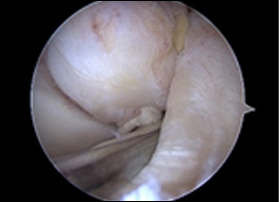

관절 내시경으로 본 정상 십자인대